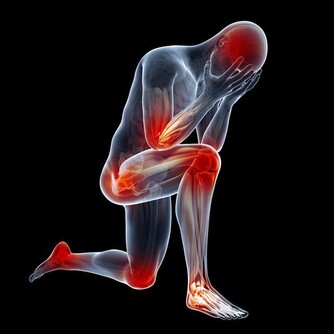

*****7.歐米茄3s*****

這些脂肪酸被稱為“必需脂肪酸”,因為您的身體無法製造它們。它們對您的眼睛,大腦和精子細胞很重要。它們還可以幫助預防與年齡有關的疾病,例如老年癡呆症,關節炎和黃斑變性,這些疾病可能導致失明。從脂肪魚,核桃,低芥酸菜籽油或亞麻籽等食物中能獲取。